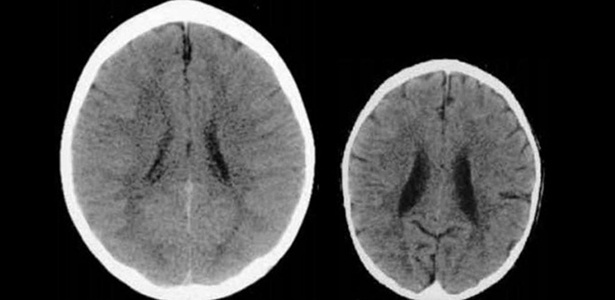

Existem muitas pesquisas, estudos de profissionais renomados que provam os danos que a violência na criação gera (como Daniel Goleman, George Holden, Daniel Siegel) e ainda provam como afeta o desenvolvido neurológico. O livro “Crianças Dinamarquesas” cita resultados de algumas pesquisas: “as crianças que apanham podem se sentir deprimidas ou desvalorizadas e ter autoestima prejudicada. Surras acabam saindo pela culatra, pois estimulam a criança a mentir, no desespero de evitá-las. O castigo físico está relacionado a problemas de saúde mental na vida adulta, incluindo depressão, ansiedade, uso de drogas e alcoolismo. Há evidências por neuroimagem de que pode afetar as regiões do cérebro relacionadas ao desempenho em testes de Q.I. e existem dados que sugerem que pode afetar regiões do cérebro relacionadas ao controle do estresse e das emoções”.